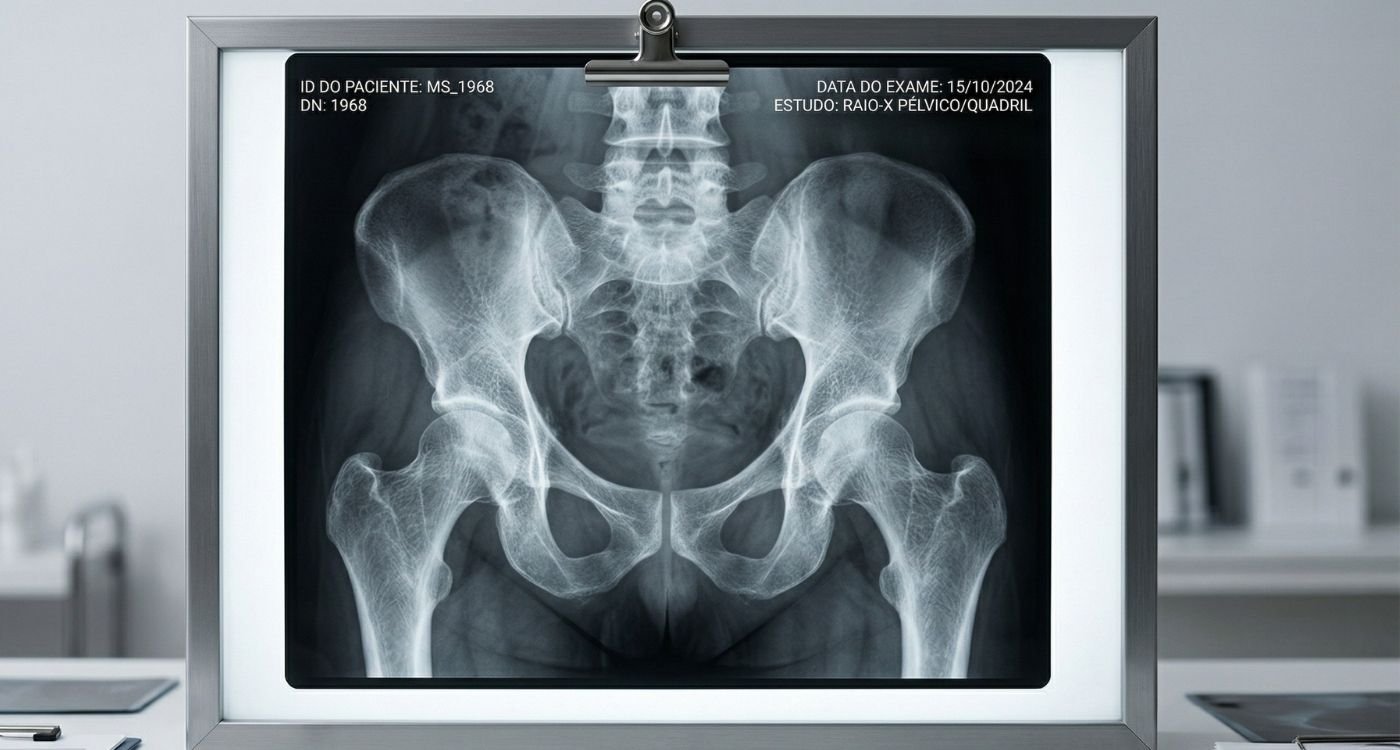

A densitometria óssea é um exame importante para avaliar a densidade mineral dos ossos e ajudar no diagnóstico de osteopenia e osteoporose.

A decisão não deve se basear só na idade. O conjunto da história clínica é o que define melhor o momento de investigar.